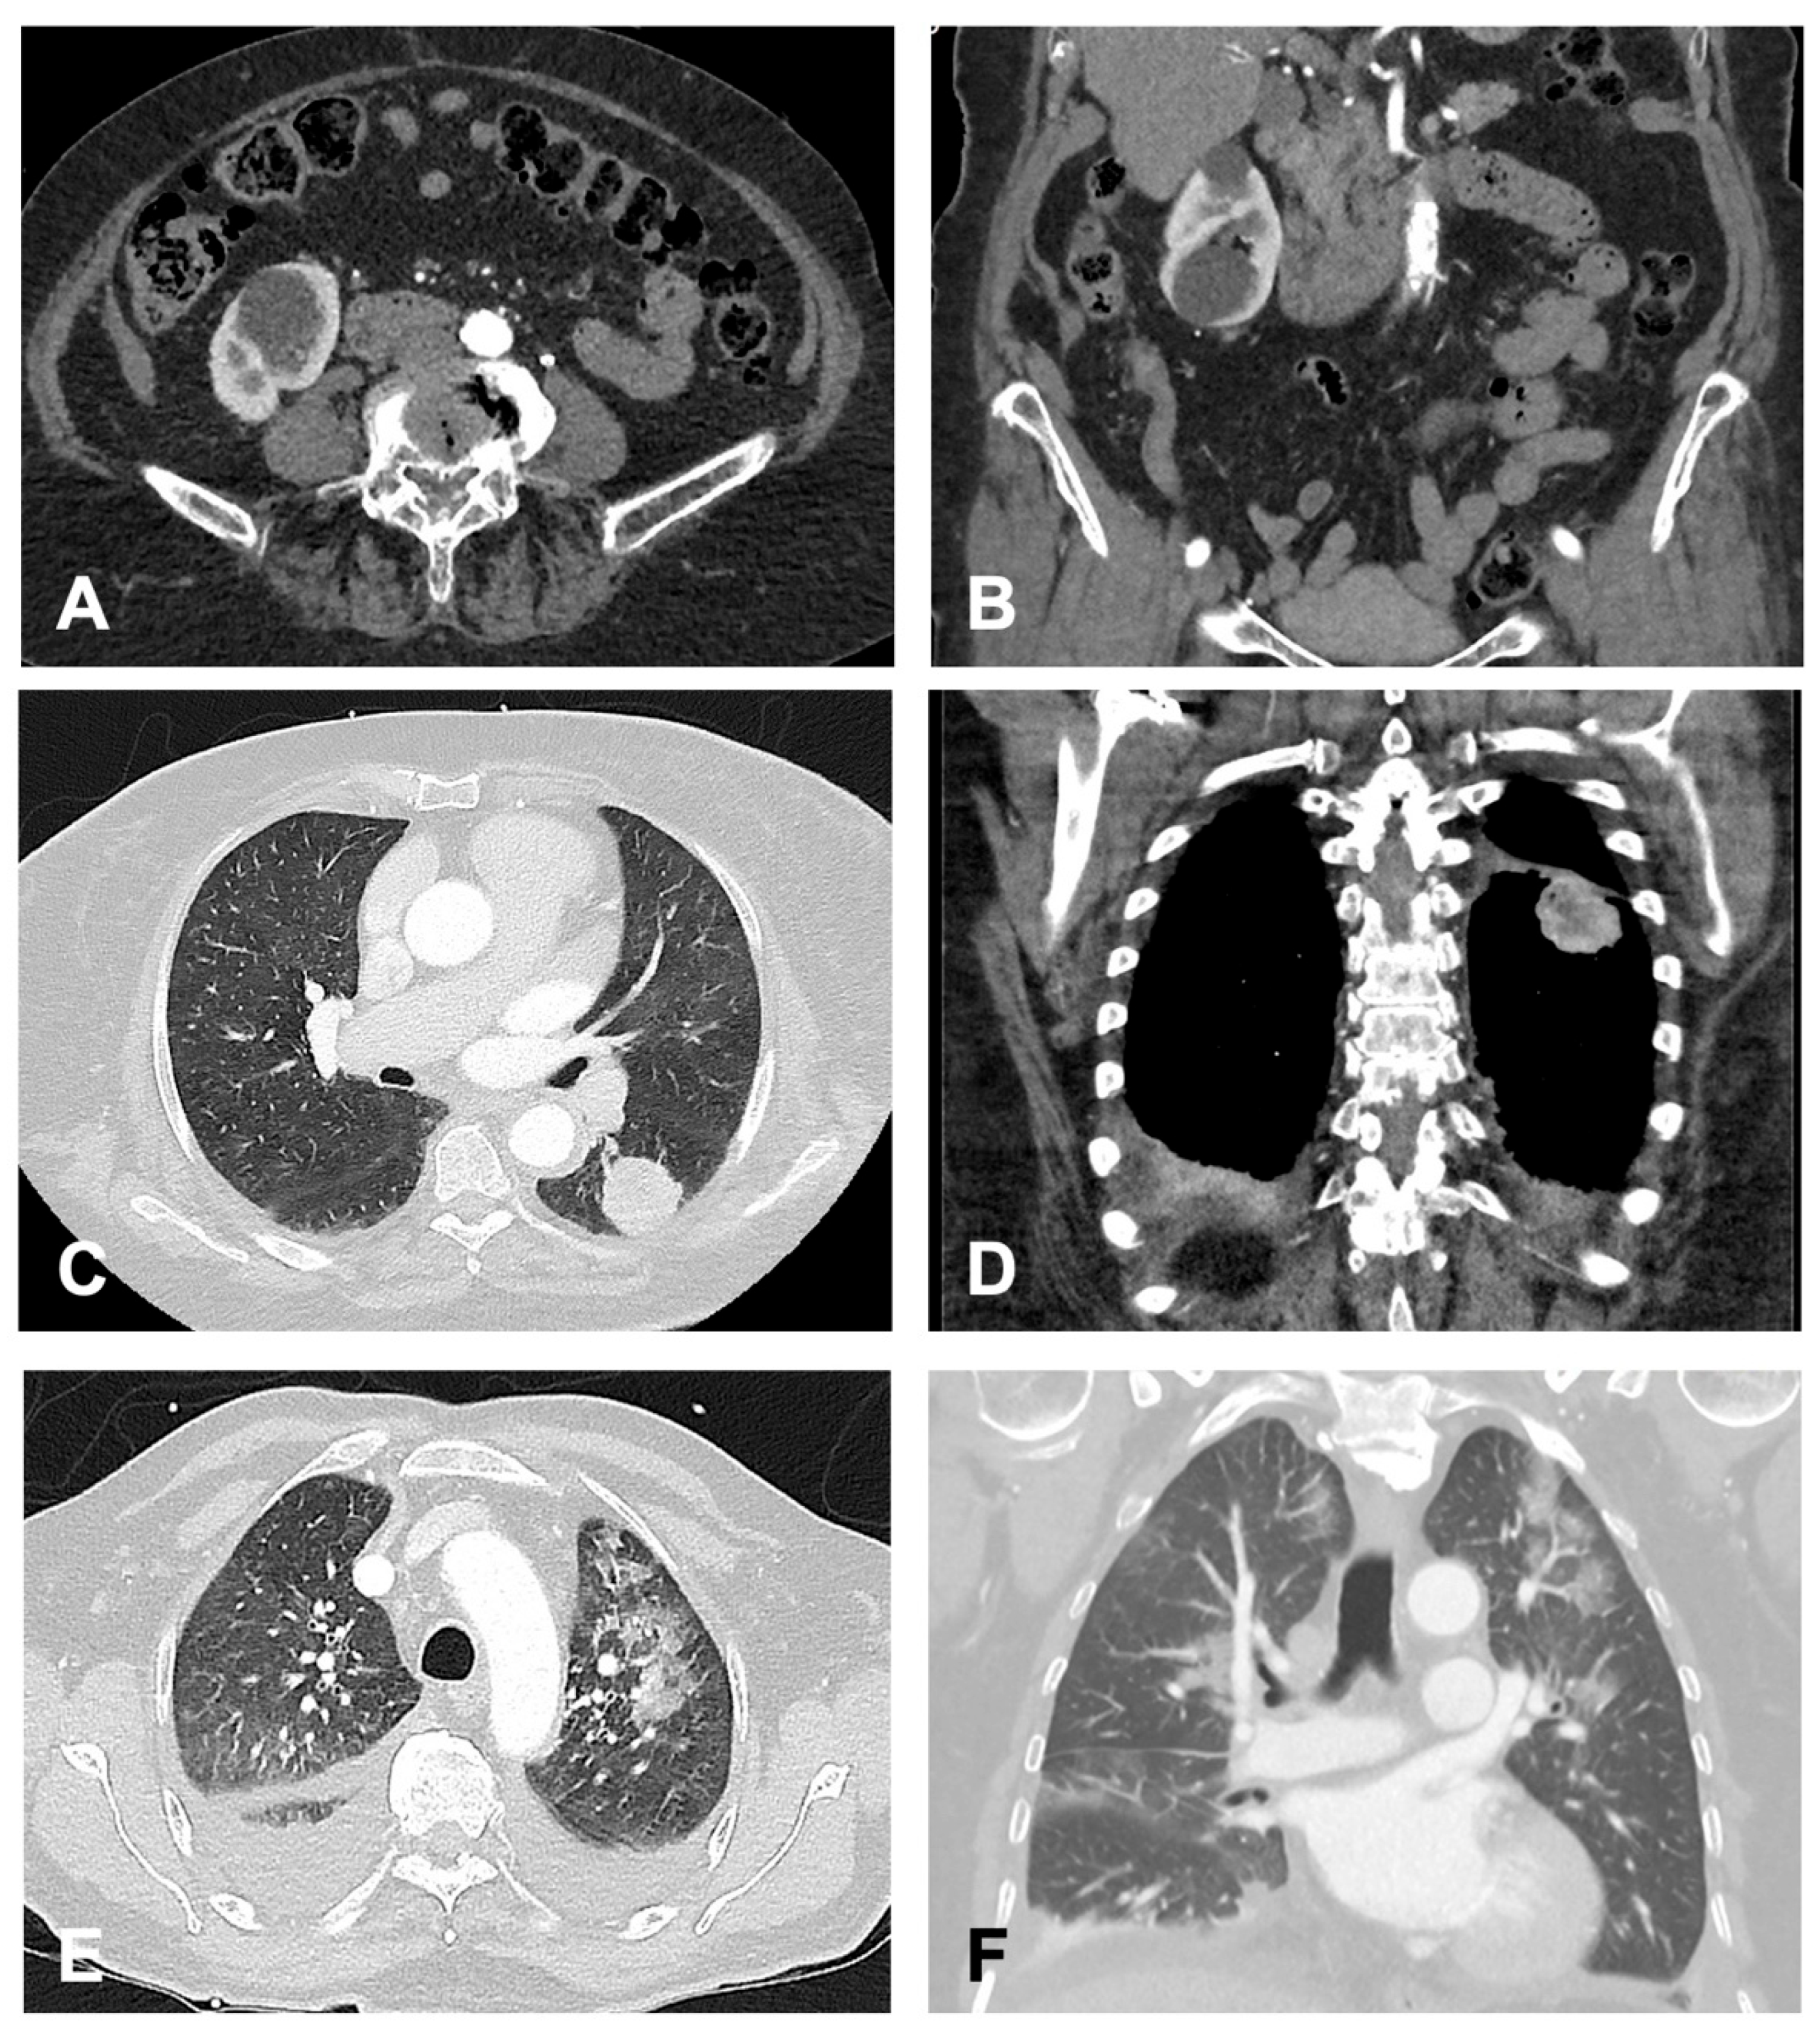

Additionally, Figure 3 provides representative CT images for selected findings from each category, highlighting examples of benign, indeterminate, and clinically significant incidental findings.

Figure 3. Exemplary Findings of Categories (AC), Each Shown in Transverse and Coronal Planes. (A,B) (Group A): 82-year-old female patient with incidental right-sided renal cysts. (C,D) (Group B): 74-year-old female patient with an incidentally detected mass in the apical segment of the left lower lobe. Subsequent histopathological examination confirmed an adenocarcinoma. (E,F) (Group C): 72-year-old male patient with detected bilateral pneumonic infiltrates. Additionally, bilateral pleural effusions with adjacent ventilation impairment were observed. Given the suspicion of nosocomial pneumonia, antibiotic therapy was initiated.